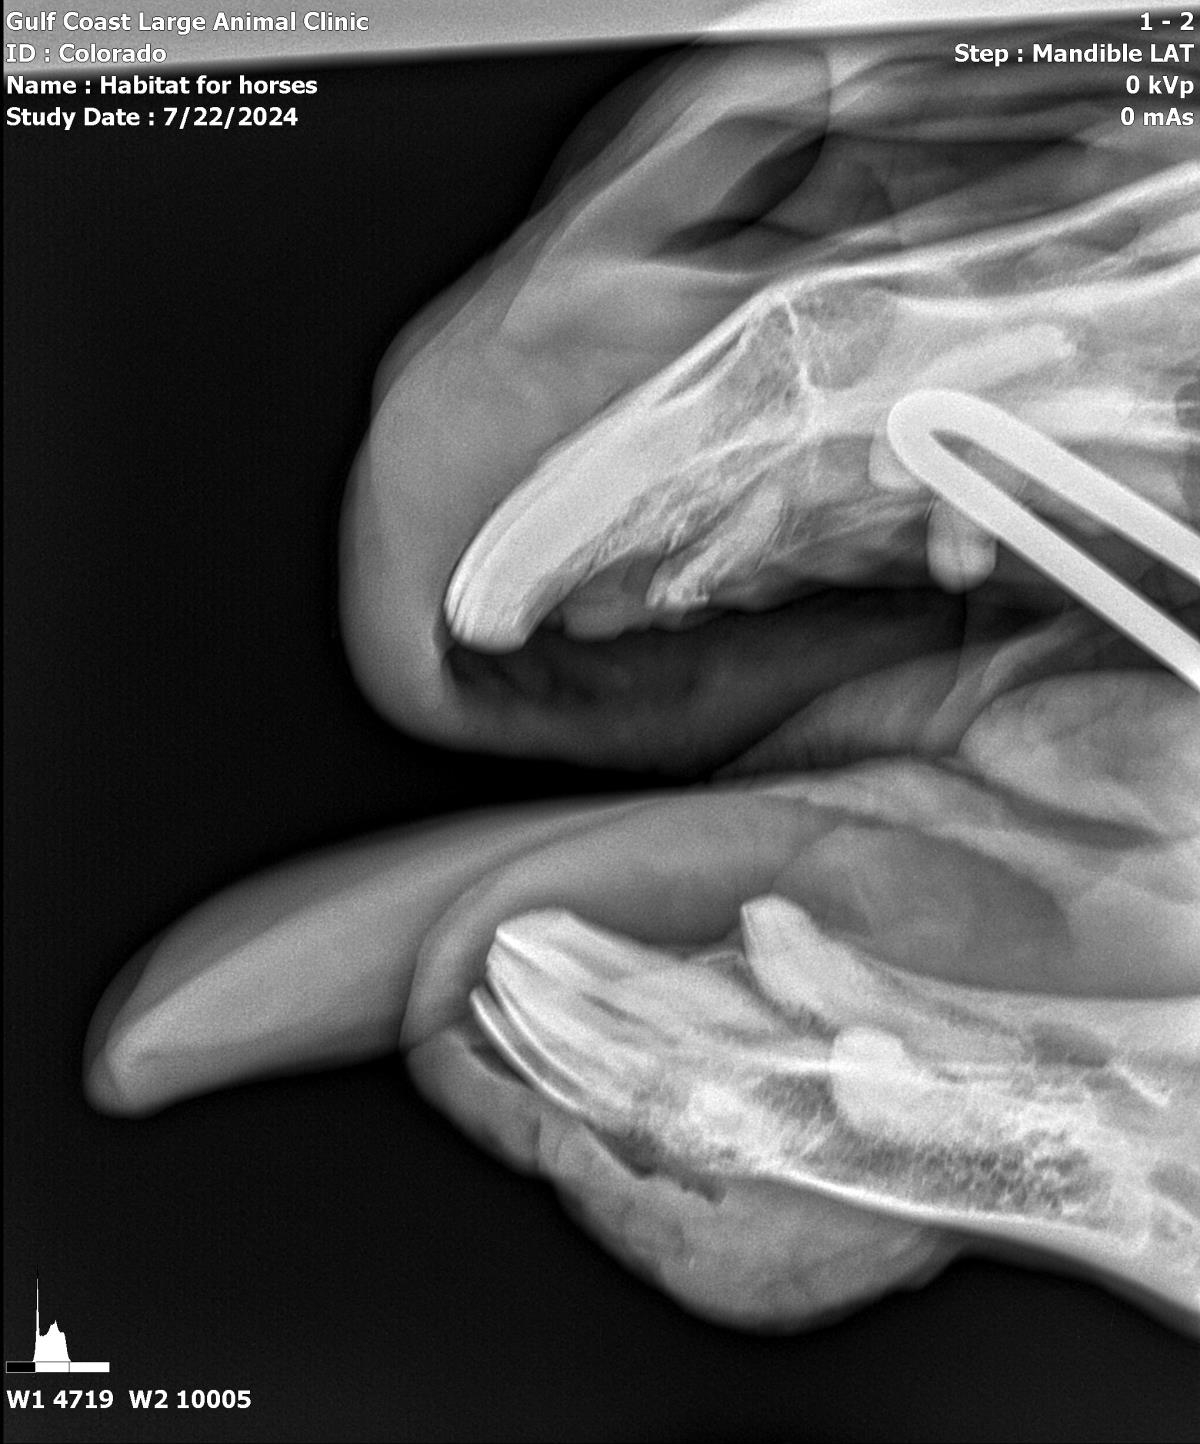

Pinto Colorado #21-010: Male Horse

Pinto Colorado

ID: 21-010 Horse

Breeds: Paint

Color: Bay & White Star

Age: 22 years (approx.)

Weight: 1,017 lbs.